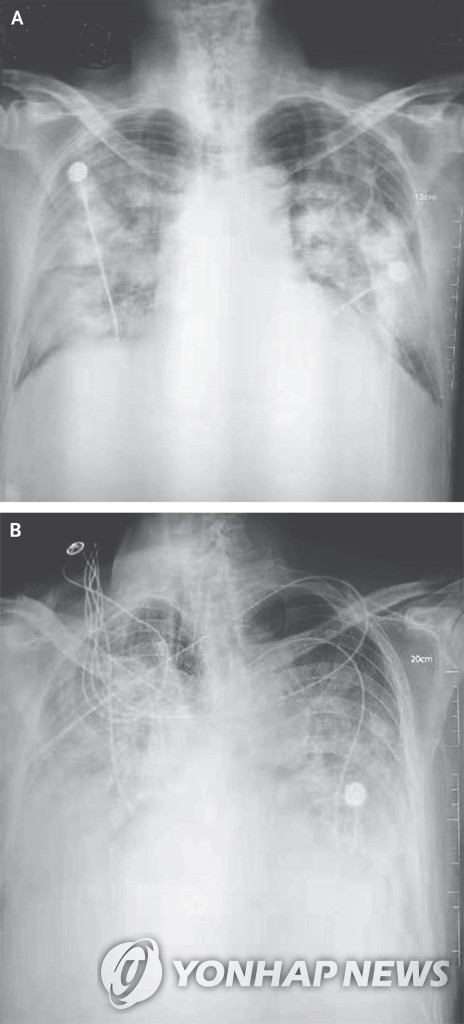

환자가 병원에서 일반적인 방식(후전위 또는 전후위 자세)으로 가슴 X선 촬영을 하면, AI 알고리즘이 영상을 분석해 폐 이상 소견과 위치 등을 의료진에게 알려준다.

AI가 검출할 수 있는 이상 소견은 ▲결절(폐에 생긴 작은 혹) ▲경화(폐 조직 일부가 딱딱하게 굳는 현상) ▲간질성 음영(폐 조직 사이 공간에 이상이 생겨 X선 영상에서 비정상적으로 보이는 부분) ▲흉막삼출(폐를 둘러싼 막 사이 공간에 물이 차는 현상) ▲기흉(폐에 구멍이 생겨 공기가 새어 나오는 상태) 등 5가지 주요 질환이다.

특히 크기가 작거나 다른 구조물에 가려져 사람 눈으로는 놓치기 쉬운 미세한 병변을 AI가 발견해냄으로써 진단 정확도를 높일 수 있다.